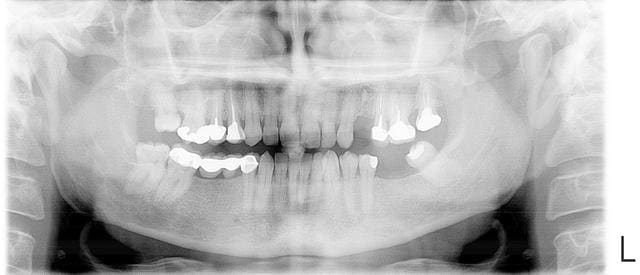

Sur le cas en bas, implantation en mai, couronne posée aujourd'hui.Il y avait un apex residuel avec un petit granulome.

Perso je déposerai la couronne et tenterai un retraitement,

si c'est ok j'attendrai 5/6 semaines puis extraction implantation,

ou alors endo puis dans la même séance extraction et implant 6 semaines plus tard.

si endo pas ok, je déciderai d'extraire les 2 dents;

et implantation immédiate si tu maîtrise la technique exo implantation,

sinon extraction et implants 6 semaines plus tard.

Les 2 techniques fonctionnent très bien, après c'est juste un gain de temps pour toi et ton patient et une réduction des chirurgies.